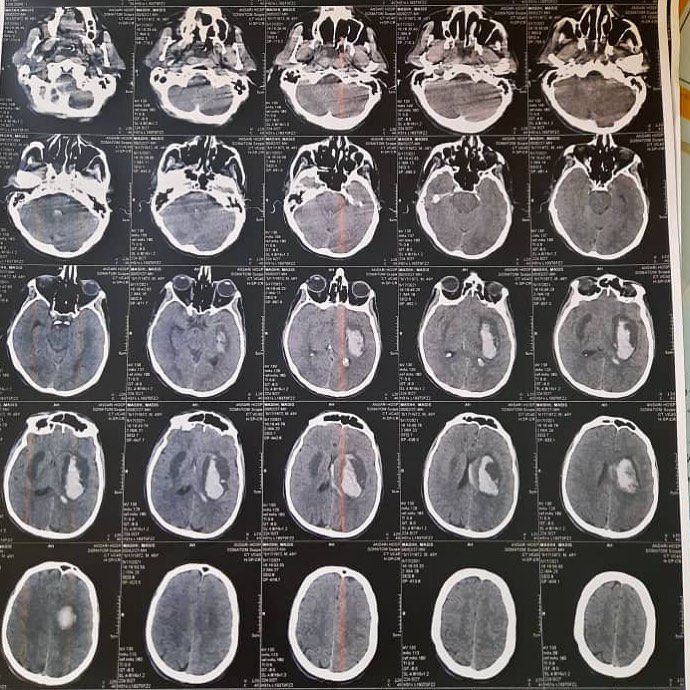

This is a CT scan of a young man's brain that has been poisoned with methanol. He is currently hospitalized in the ICU and is in a coma, free from the hustle and bustle of the world. This young man did not know the day before while consuming alcohol that he was consuming methanol instead of ethanol. But the manufacturer and distributor knew exactly what was in the bottle 🥺I do not know how likely this young boy is to survive, But I know that even if he stays, he will no longer have an eye to see, a foot to walk on, and a kidney to live ... 😑 Fake (fake) is very common these days .. Fake people, fake vaccines and drugs, fake masks, fake alcohol .. Be careful not to damage our brain and soul...

This is intracerebral hemorrhage with large perifocal oedema with uncal and transtentorial herniation, did methanol destroy the blood brain barrier which lead to ICH?